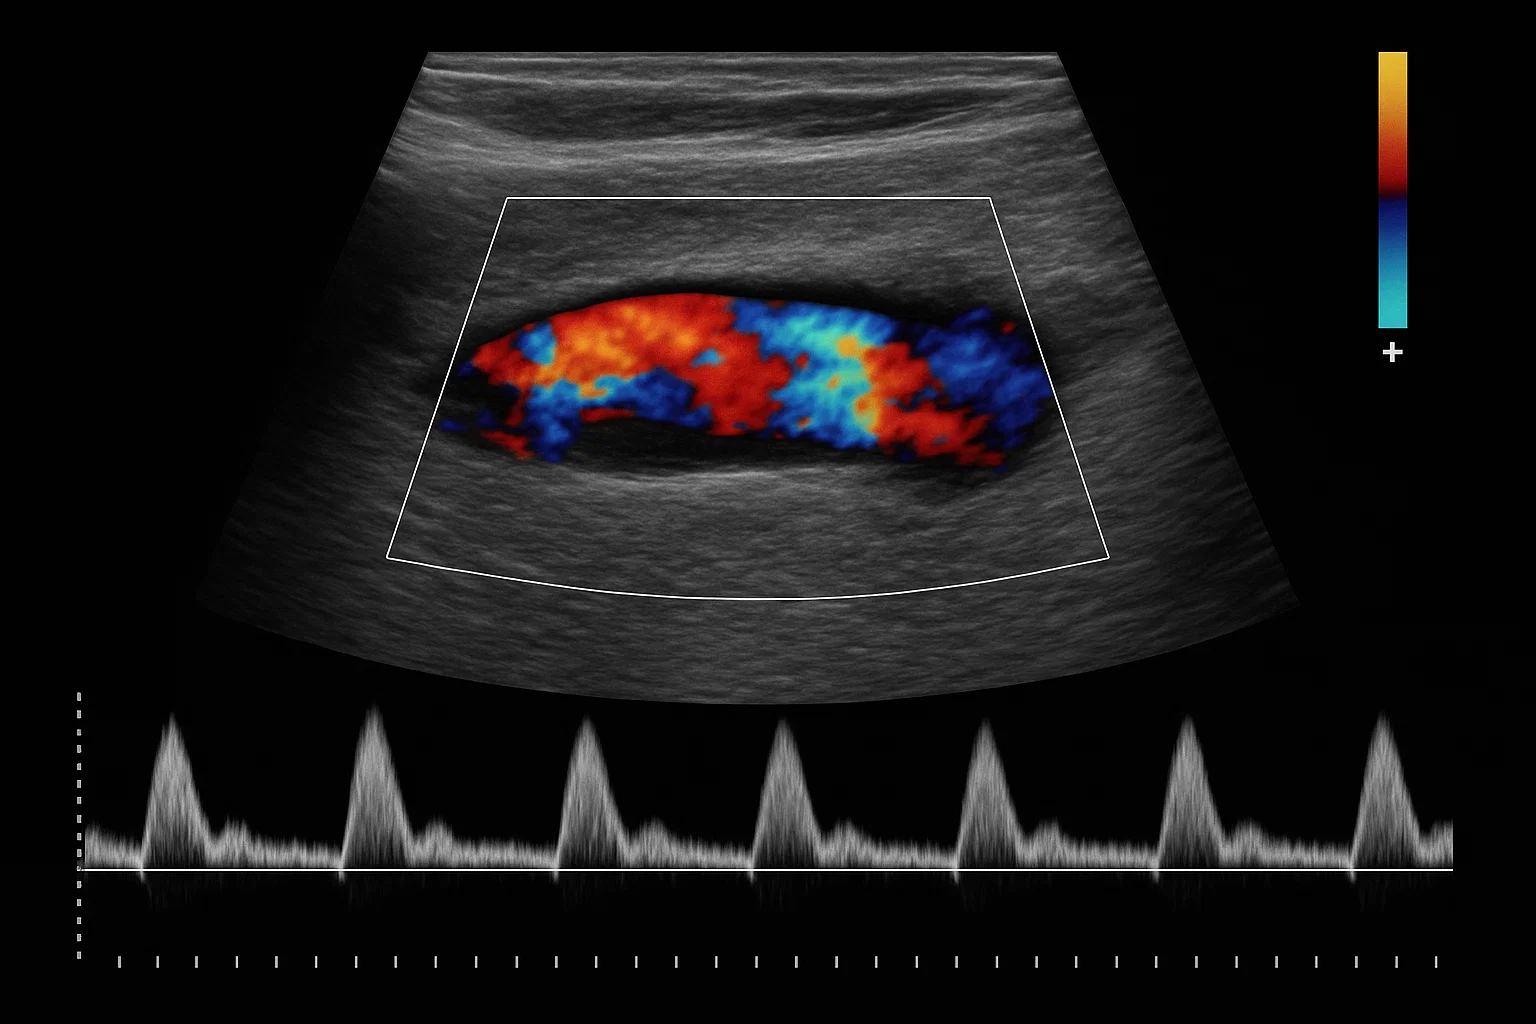

• کالر داپلر (Color Doppler): این رایج‌ترین و شناخته‌شده‌ترین نوع داپلر است. در این روش، کامپیوتر دستگاه، اطلاعات مربوط به جهت و سرعت جریان خون را به رنگ‌های مختلف تبدیل کرده و روی تصویر سیاه و سفید سونوگرافی معمولی قرار می‌دهد.4 طبق یک قرارداد استاندارد، رنگ قرمز نشان‌دهنده جریان خون به سمت پروب (مبدل) و رنگ آبی نشان‌دهنده جریان خون در جهت مخالف آن است (قانون BART: Blue Away, Red Toward).5 شدت و روشنایی رنگ نیز می‌تواند نشان‌دهنده سرعت جریان باشد. این نمایش بصری و رنگی به پزشک اجازه می‌دهد تا به سرعت و به صورت شهودی، محل، جهت و وجود جریان خون را در یک ناحیه وسیع ارزیابی کند.

• داپلر طیفی (Spectral Doppler): این روش، دقیق‌ترین و کمی‌ترین اطلاعات را در مورد جریان خون ارائه می‌دهد. به جای نمایش رنگی، داپلر طیفی اطلاعات جریان خون را به صورت یک نمودار گرافیکی نمایش می‌دهد که در آن، سرعت خون (در محور عمودی) در طول زمان (در محور افقی) رسم می‌شود.8 این نمودار که “شکل موج داپلر” نامیده می‌شود، به پزشک اجازه می‌دهد تا تحلیل‌های بسیار دقیقی از الگوهای جریان خون انجام دهد، سرعت دقیق خون را اندازه‌گیری کند و شدت تنگی (استنوز) یا نارسایی (رگورژیتاسیون) را به صورت کمی مشخص نماید.